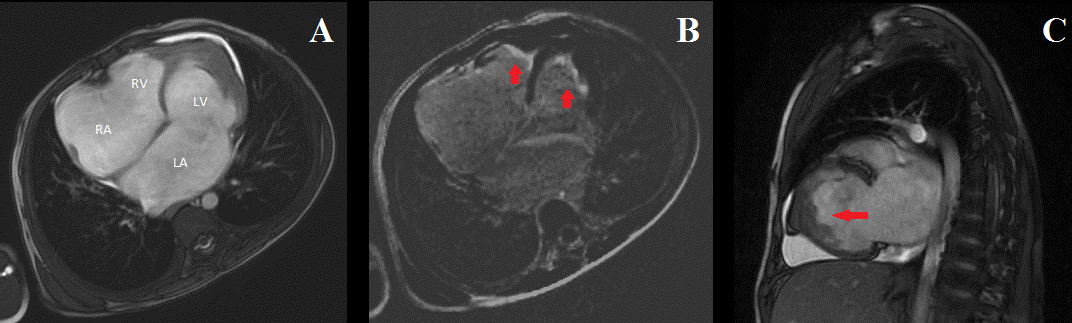

We report a case of a 7-year-old boy, without medical history, who presented a low weight-to-height ratio associated with effort dyspnea class III and hepatalgia. The physical examination objectified signs of right sided heart failure including jugular venous dilatation, congested hepatomegaly, an ascite, without peripheral oedema. At cardiac auscultation, the heartbeats were well perceived, with a breath of tricuspid regurgitation (grade 4/6). The blood pressure was 100/60 mm Hg. The pulmonary auscultation was normal. The electrocardiogram showed a paroxysmal atrial fibrillo-flutter with ventricular rate of 95 beats/min. The chest X-ray showed a cardiomegaly with an important auricles dilatation. The blood analysis objectified iron deficiency anemia and hypereosinophilia of 600/mm3. The liver and renal function tests were normal. The copro-parasitological examination was normal. Given the patient poor echo window, the transthoracic echocardiography hardly objectified, in two-dimension mode, dilated atria and hyperechogenic dense biventricular apical fibrosis. The systolic function of left ventricle and right ventricle was normal. The doppler echocardiography showed tricuspid and mitral restrictive inflow patterns with moderate pulmonary hypertension. The diagnosis of endomyocardial fibrosis was made and consolidated by findings of the cardiovascular magnetic resonance imaging (CMR) that objectified a restrictive cardiomyopathy with dilated atria and biventricular apical obliteration (A). In delayed enhancement sequences, we found apical sub-endocardial late gadolinium enhancement involving both the left ventricle and the right ventricle suggesting fibrosis (B) with left ventricular apical thrombus (C). The patient has received a medical therapy including diuretics and anticoagulant and was referred to undergo endocardiectomy.